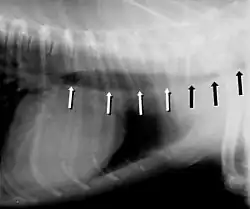

Symptoms include a cough (often called a "goose honk cough" due to its sound), especially when the dog is excited. This cough is usually paroxysmal in nature. Other symptoms include exercise intolerance, respiratory distress, and gagging while eating or drinking. Tracheal collapse is easily seen on a radiograph as a narrowing of the tracheal lumen. Treatment for mild to moderate cases include corticosteroids, bronchodilators, and antitussives. Medical treatment is successful in about 70 percent of tracheal collapse cases.[4] Severe cases can be treated with surgical implantation of a tracheal stent (inside or outside of the trachea) or prosthetic rings. Extraluminal (outside the trachea) stenting is generally used only for tracheal collapse in the neck region. Intraluminal stenting has shown more promise for success with intrathoracic cases, especially using nitinol, a type of shape memory alloy composed of nickel and titanium. Potential problems include stent migration and fracture.[5]